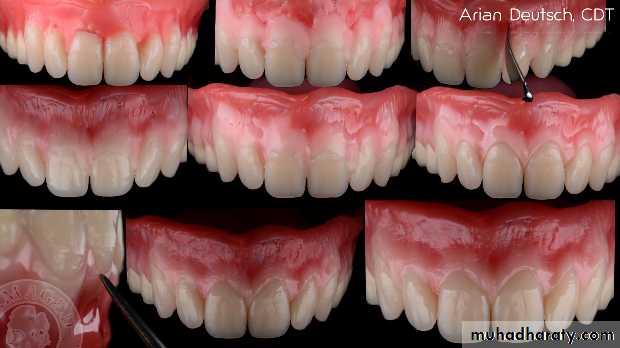

*Bronzed skin – addison’s diseaseLIP EXAMINATION:

Lip support

Lip lengthLip thickness

Lip mobility

Health of the lips

LIP SUPPORT – adequately supported

- unsupportedContour and appearance of the

vermillion border usually are alteredby tooth loss

Placement of anterior teeth

If the anterior teeth are set too far lingually or palatally, lips will lack the necessary support.

Unsupported lip